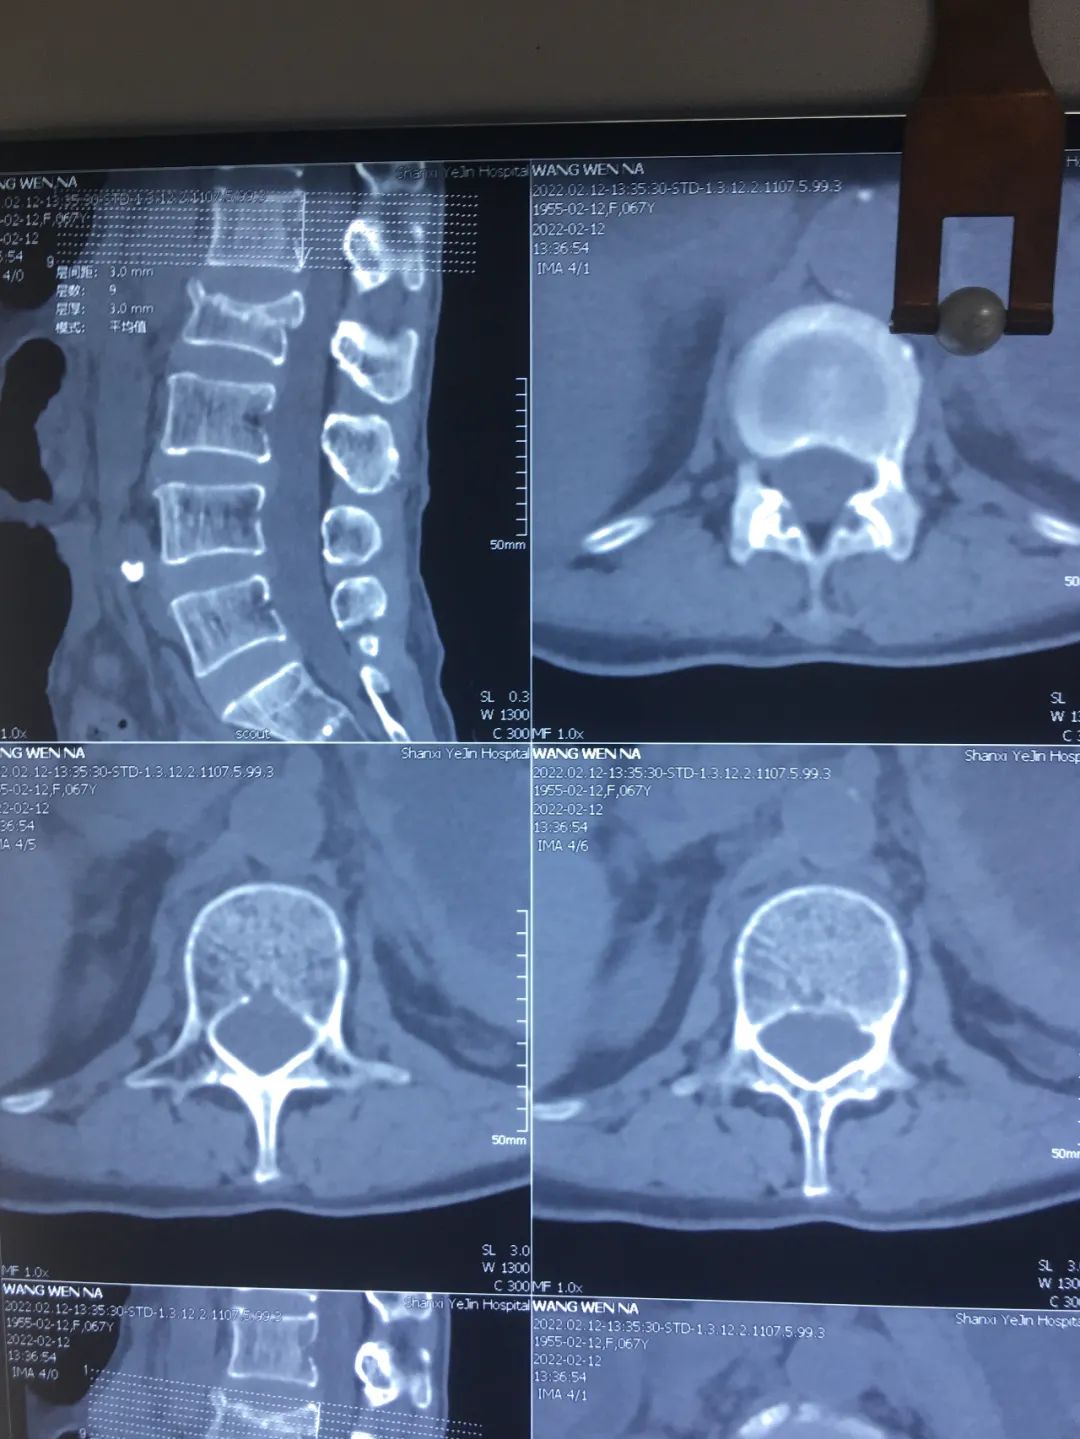

2月12日,家人将她送到陕西冶金医院就诊。医生完善相关检查,拍片提示:腰2椎体新近压缩性骨折,遂收住骨科。

检查中发现王阿姨腰2椎体新近压缩性骨折,右下腹肠管积气,麻痹性肠梗阻,特邀外科会诊。结合王阿姨情况,立即制定最佳手术治疗方案。